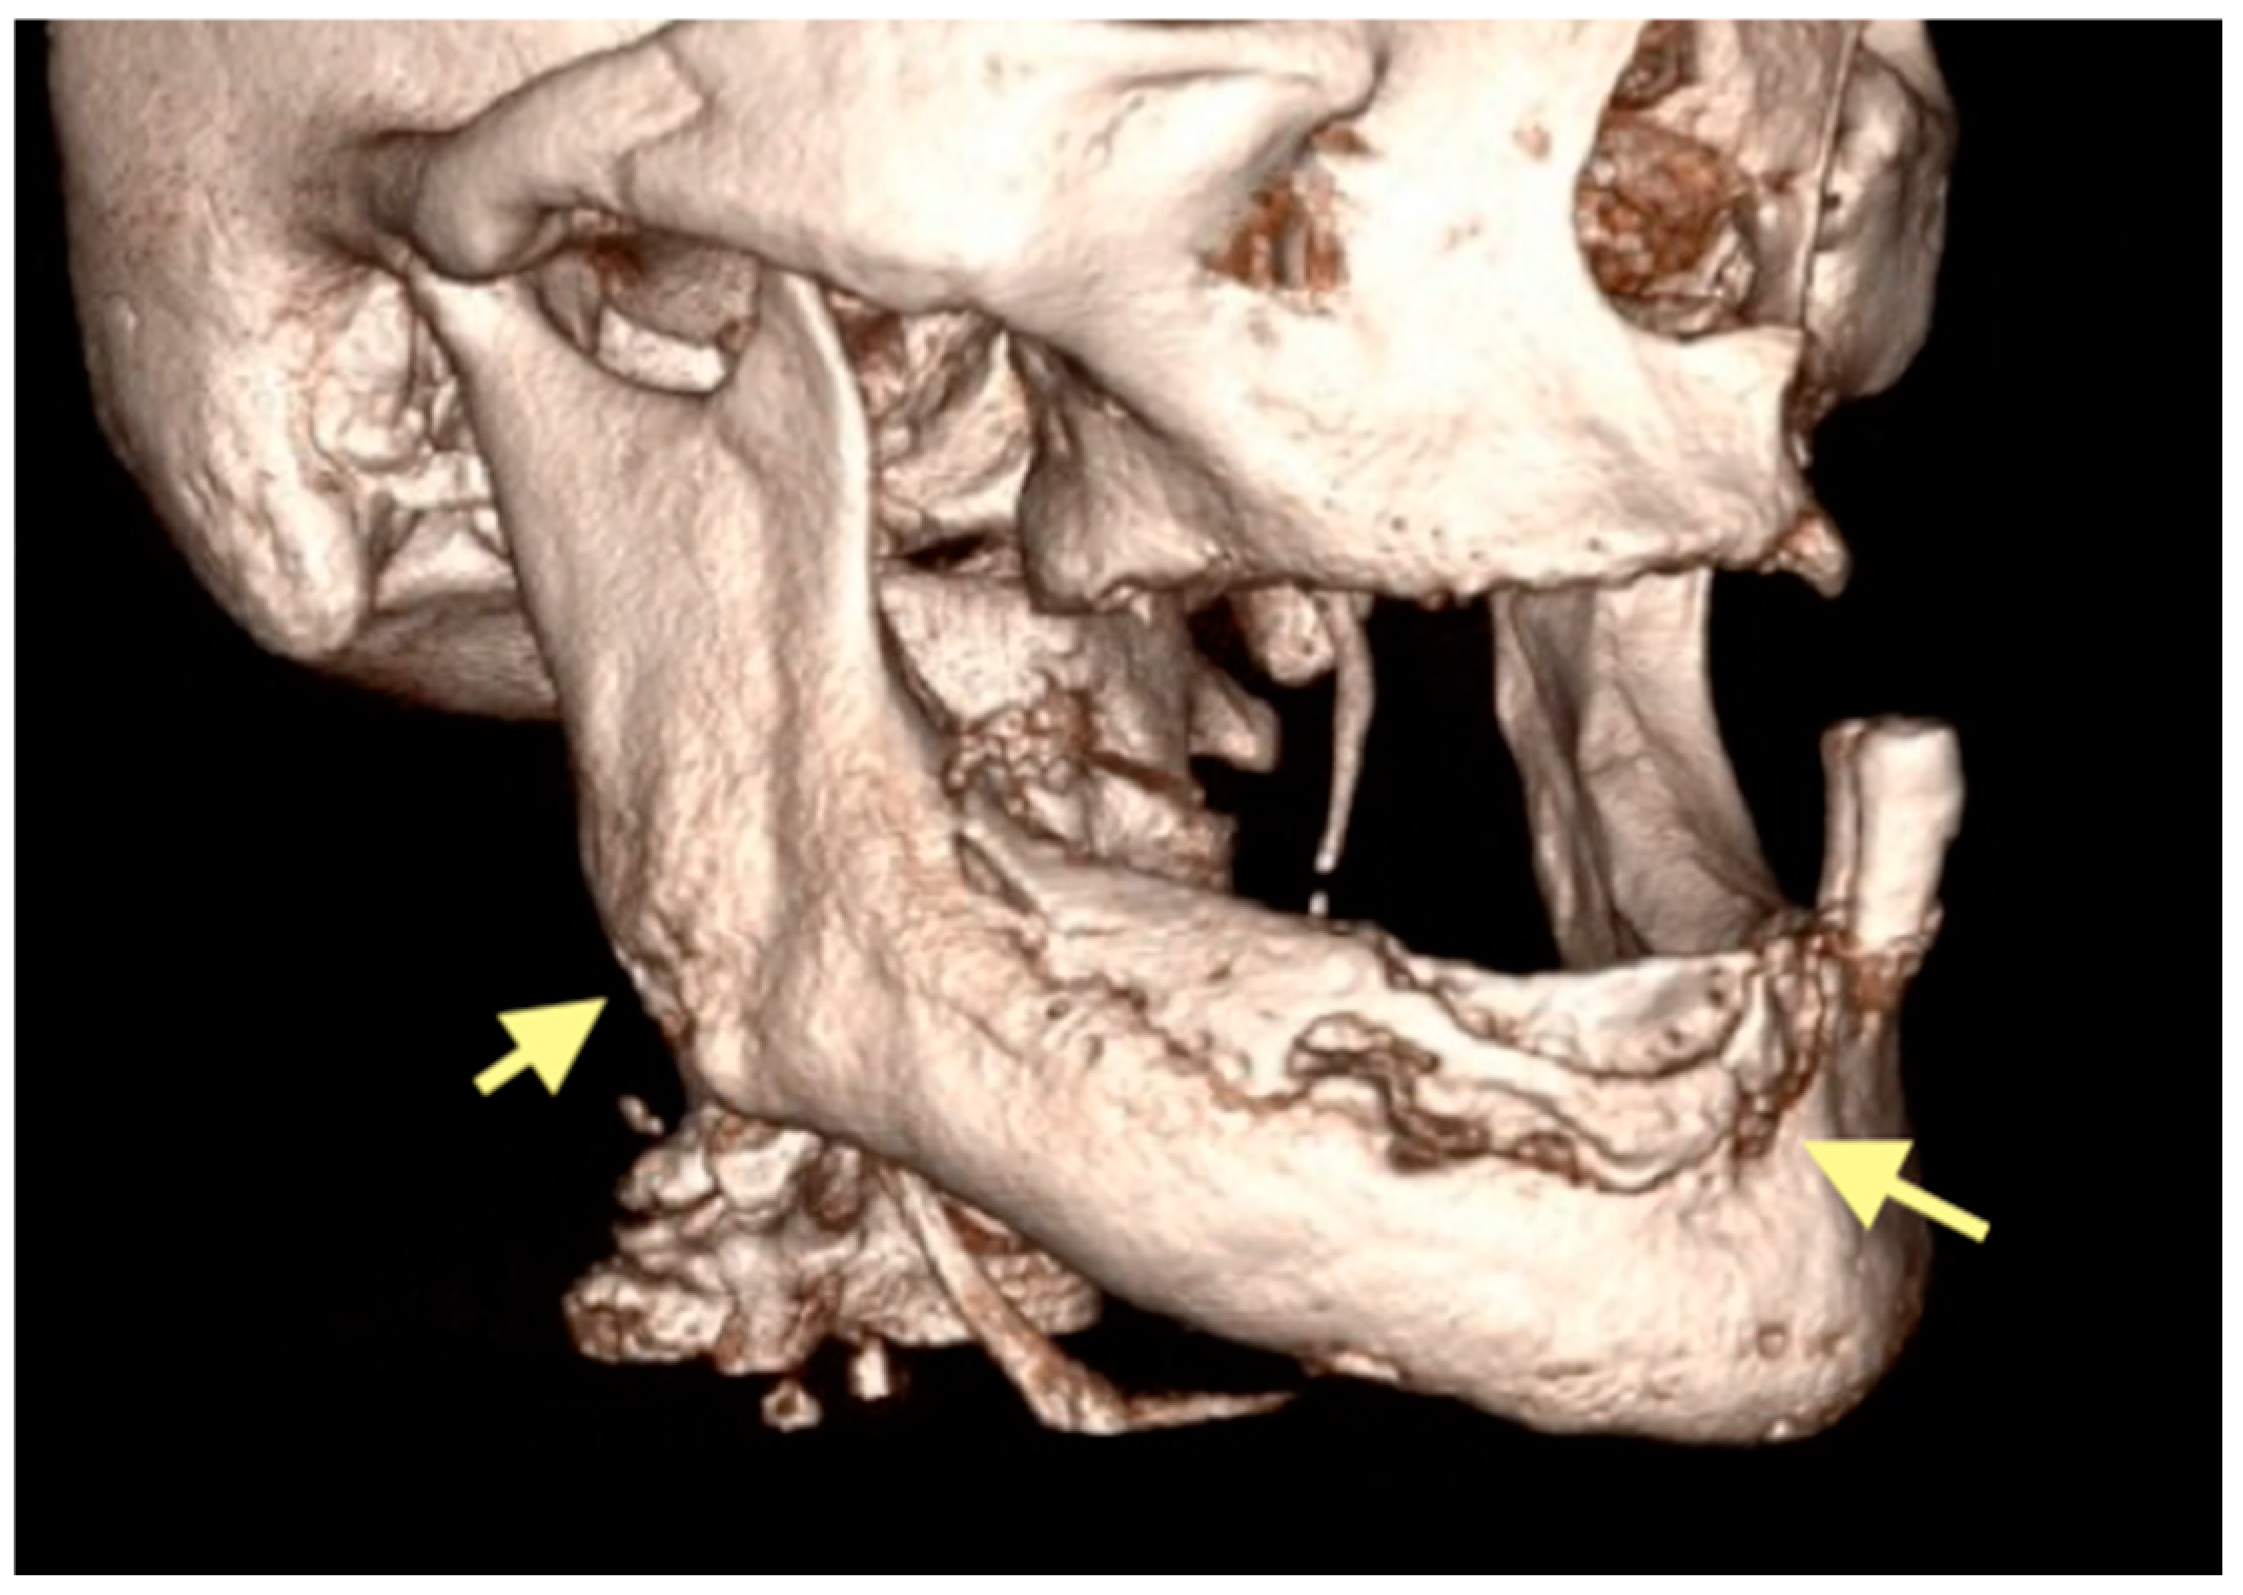

The third patient was a 75-year-old female with osteonecrosis of the mandible and maxilla in the fourth and in the second quadrant (see Figure 7, Figure 8 and Figure 9). The patient had third-stage jaw osteonecrosis. In 2023, the patient was diagnosed with osteonecrosis of the upper and lower jaw caused by antiresorptive therapy (until August 2021, the patient regularly used Zolendronic acid; then, this drug was replaced by the RANKL inhibitor Denosumab). The treatment was periodically complicated by submandibular and submental abscesses. In addition, due to the progression of the underlying disease, constant courses in chemotherapy were administered. The patient underwent three operations, which included sequestrectomy of the jaw with simultaneous use of A-PRF, antrotomy with revision of the maxillary sinus, closure of the oroantral communication, and opening and revision of abscesses of the soft tissues (see Figure 10 and Figure 11)

Figure 8.

CT of the head and facial bones (16 December 2024).